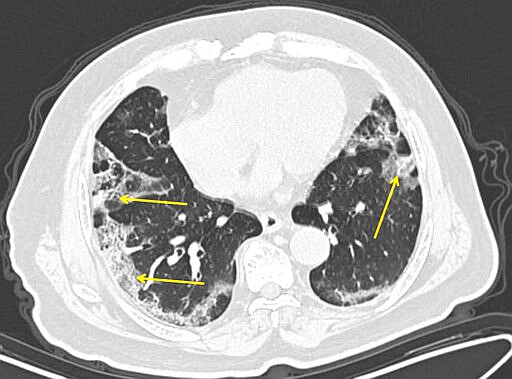

Doctors at New York’s Mount Sinai Health System analyzed 121 chest CT scans shared by colleagues in China and spotted something unusual.

Healthy lungs look mostly black on medical scans because they’re full of air. An early infection with bacterial pneumonia tends to show up as a white blotch in one section of one lung. Pneumonia caused by a virus can show up as hazy patches that go by a weird name -- “ground glass opacities.”

In people who get COVID-19 pneumonia, that haze tends to cluster on the outside edge of both lungs, by the ribs, a distinctive pattern, said Dr. Adam Bernheim, a radiologist at Mount Sinai.

As infection worsens, the haze forms rounder clusters and gradually turns more white as the air sacs become increasingly clogged.